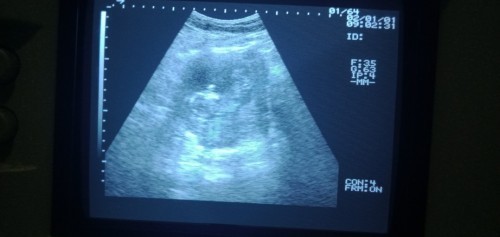

Ini saya usg yg ke 13 Minggu bun.tpi Sya blom bgtu jelas liat dd nya. ππ€

itu kliatan bun klo mau lebih jelas yg 4D USg nya

ihh bund itu keliatan πππ